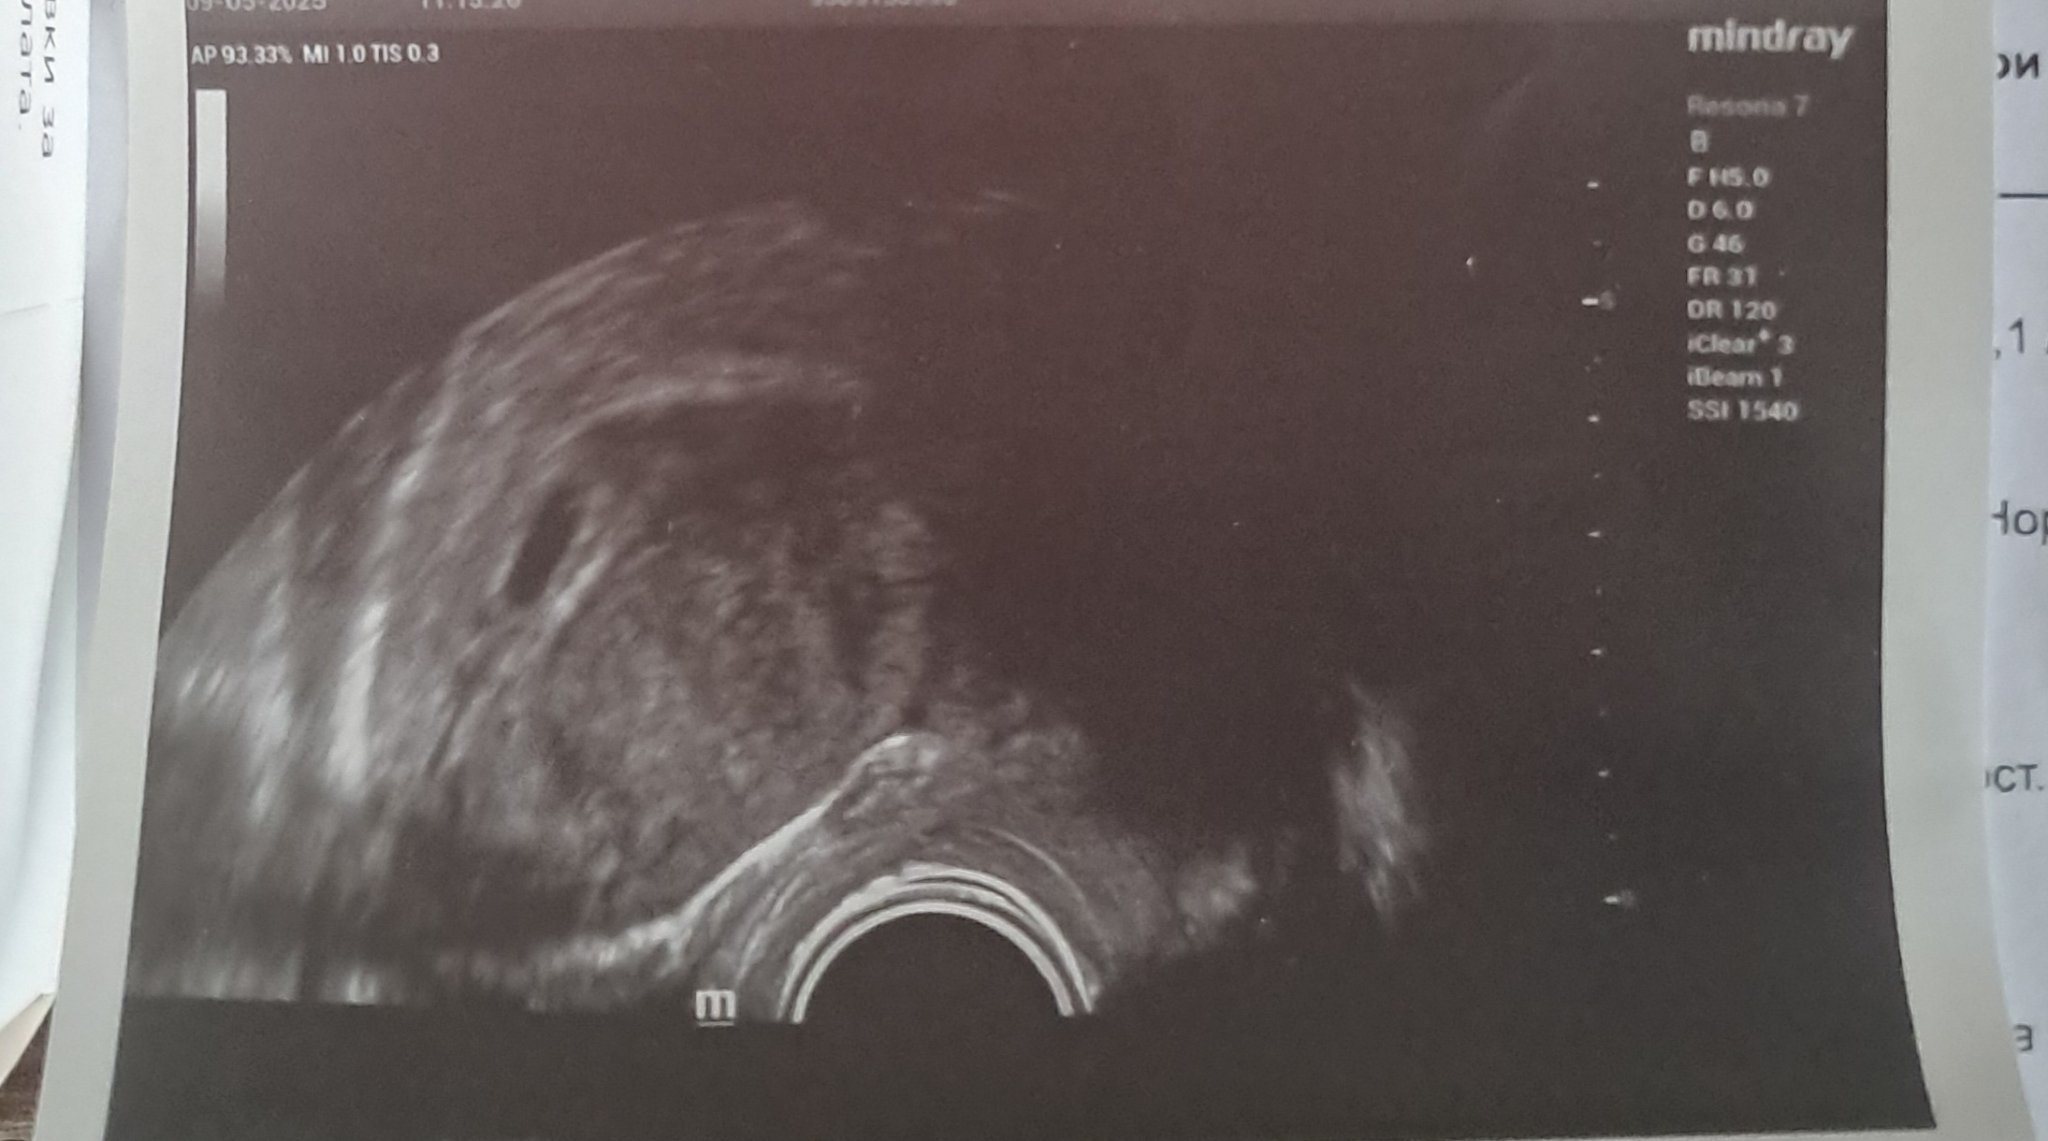

Здраейте днес бях на лекар в 8-ма г.с съм все още не се вижда ембриомът казаха ми да отида в петък на лекар за да се види... притесявам се много тъй като ми е 1- ва бременност и сме го чакали 3 години

Идете при друг с по-добра апаратура. В 8 г.с. трябва и пулс да има.

Veronikaaaa,ако са ви преглеждали с коремен ехограф възможно е,но с вагинален няма как да не се види ембрион в 8 г.с.